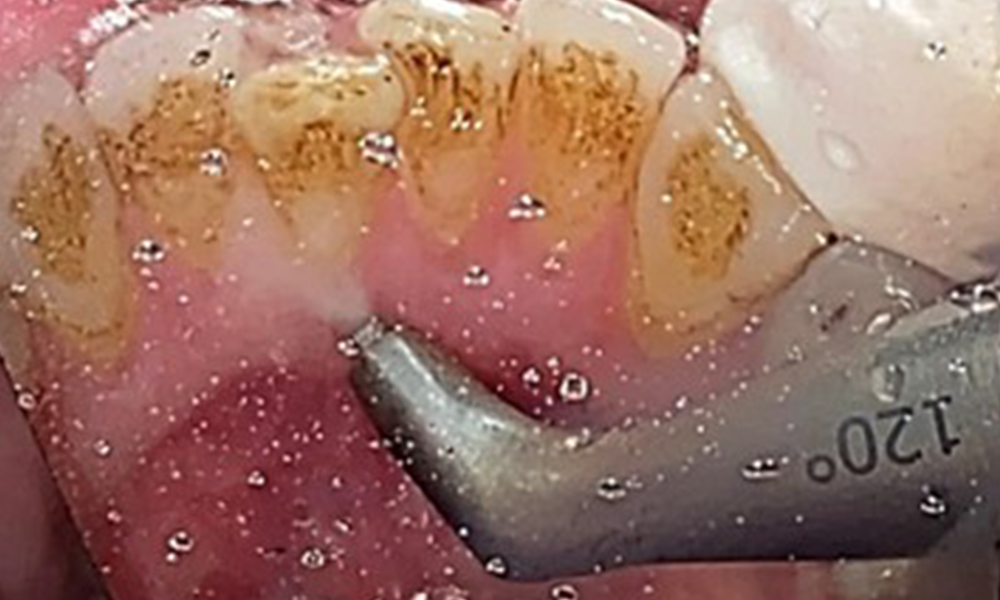

Ziel ist es durch supra- und subgingivale Biofilmentfernung das Erkrankungsrisiko zu kontrollieren. Die Wahl der Instrumente erfolgt

bedarfsgerecht. Zunächst sind Zahnstein und ggf. Konkremente mit Ultraschall und / oder Handinstrumenten zu entfernen (Abb. 10).

Anwendung eines piezobetriebenen Ultraschallgerätes in Rg 36

Abb. 10 Anwendung eines piezobetriebenen Ultraschallgerätes in Rg 36 lingual (hier Proxeo Ultra, Firma W&H), © Dr. R. Krapf